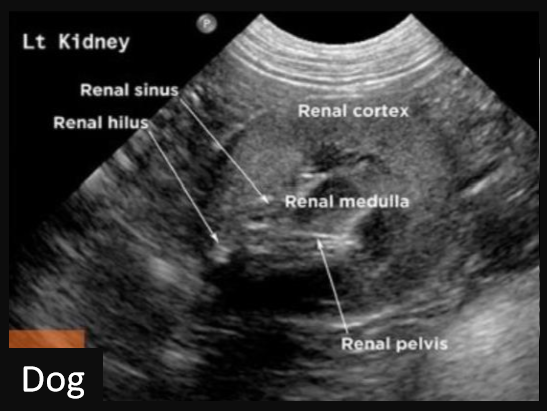

Q

Label this frontal/dorsal view kidney ultrasound